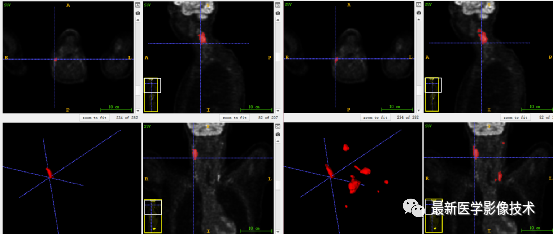

7、验证集分割结果:输入整个图像通过滑窗叠加预测结果,左图是金标准,右图是预测结果